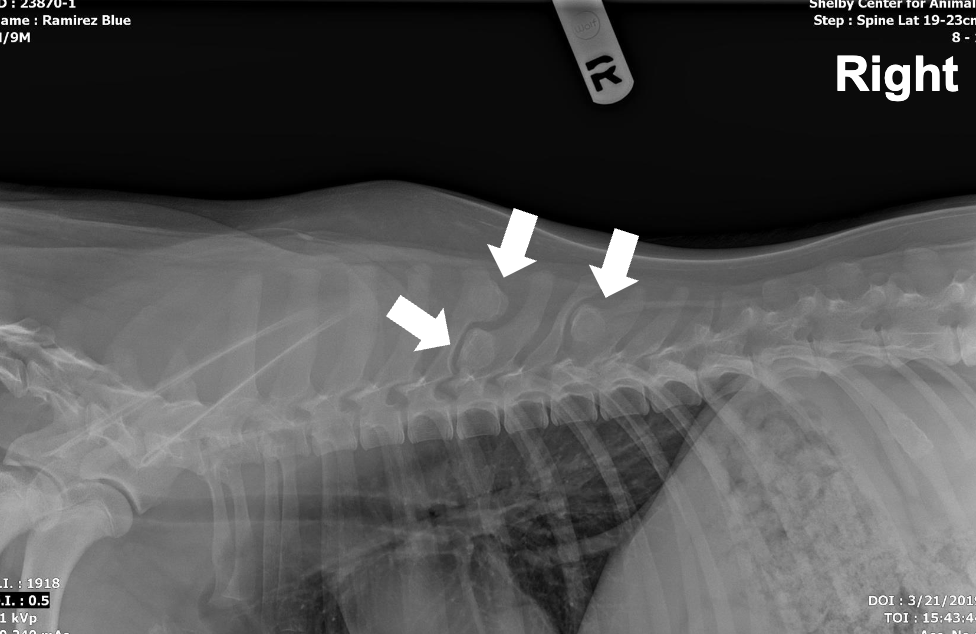

What is shown in this image?

hemivertebra

What are the characteristics of hemivertebra?

-failure of vertebral body to form completely

-can be incidental in minor cases

-can cause compression of spinal cord in severe cases

-bred for in breeds with screw tails

-causes paraparesis and incontinence at young age

-diagnosed with radiographs and advanced imaging